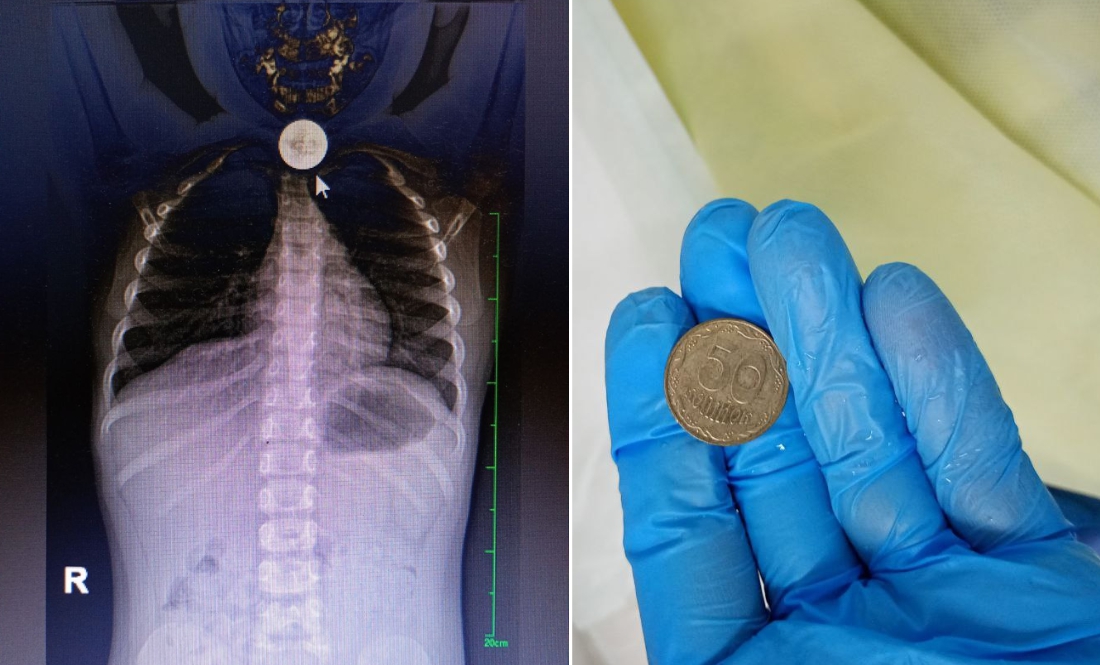

Він зазначив: на монетку в 50 копійок натрапили під час рентгенографії органів грудної клітки та черевної порожнини. Цьому передував візит до лікаря стривожених батьків.

Стороннє тіло фахівці видалили ендоскопічно.